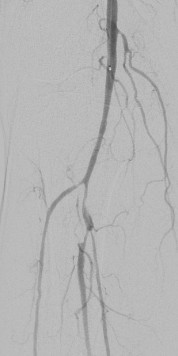

術(shù)中DSA:箭頭提示雙髂動(dòng)脈血栓栓塞,血流中斷

術(shù)中DSA:雙髂動(dòng)脈血流恢復(fù)

箭頭所示:右腘動(dòng)脈血栓栓塞,血流中斷

術(shù)后右下肢動(dòng)脈血流復(fù)通

箭頭所示:左股、腘動(dòng)脈血栓栓塞,血流中斷

術(shù)后:左股腘動(dòng)脈血流復(fù)通